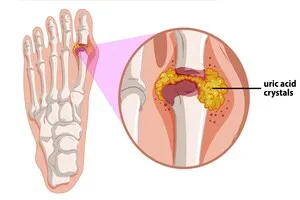

8. 통풍

혈액 내 요산 수치가 높아져 관절에 요산 결정이 쌓여 극심한 통증과 염증을 유발하는 질환입니다. 특히 엄지발가락 관절에 자주 발생하며, 붉게 부어오르고 심한 통증을 동반합니다. 붉은 육류, 내장, 등 푸른 생선, 술 등 퓨린 함량이 높은 음식 섭취가 주요 원인으로 꼽힙니다. 급성기에는 콜히친, NSAIDs, 스테로이드 등의 약물로 통증과 염증을 완화하고, 만성기에는 요산 생성을 억제하거나 배출을 촉진하는 약물을 복용합니다. 또한, 퓨린 함량이 높은 음식 섭취를 줄이고, 충분한 수분 섭취와 함께 과일, 채소를 섭취하여 요산 배출을 돕습니다. 특히 술은 요산 수치를 높이고 배출을 방해하므로 금주하는 것이 좋습니다. 적절한 체중 관리도 중요합니다.